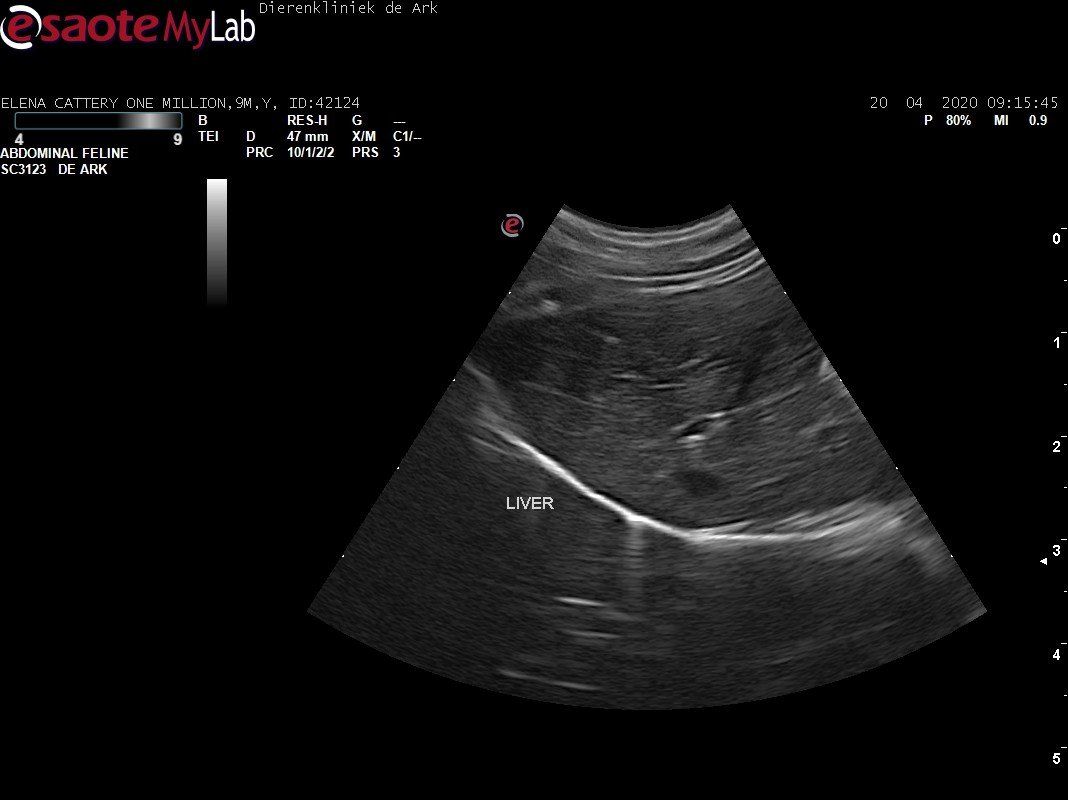

3,200 kg , echo en nieuw bloedonderzoek gedaan wat perfect ging door middel van gapabetine

Voor de garanties en om recht te hebben op medicatie bij herval eist Mutian diverse onderzoeken en controle momenten. Dit zijn bloedonderzoeken maar ook zoals hieronder te zien is echo's. Elana is volledig gecontroleerd op afwijkingen, gelukkig waren de echo's goed.